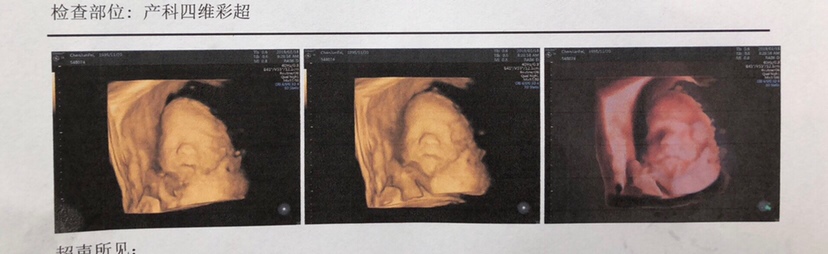

孕22周+1天